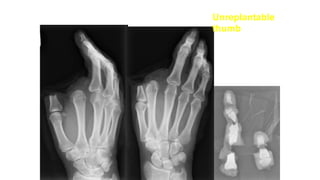

 43 year-old female, right-handed, cook

Traumatic amputation of right thumb and index finger

Underwent emergency debridement on day of injury

Unreplantable

thumb